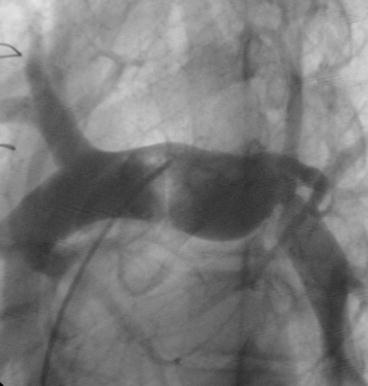

After 3 years, the girl was traced. She then underwent diagnostic angiogram, which confirmed ligation of the LPA with faint filling of the distal vessel (Fig. 2). Pulmonary artery pressure was 75/49 mmHg (mean 63 mmHg) while aortic pressure was 112/50 mmHg (mean 86 mmHg). During an overseas surgical mission, she subsequently underwent LPA reconstruction and PDA division via median sternotomy and on cardiopulmonary bypass. The LPA had been ligated just proximal to the lobar branching and a small, 3 mm distal orifice was found free from thrombus and with backflow of blood. During removal of the ligature, the fragile LPA wall disintegrated and was reconstructed with difficulty using autologous pericardium. Postoperative recovery was uneventful and she was extubated few hours after transfer to the intensive care unit. Follow-up echocardiogram 3 months later showed significant increment in blood flow through the LPA albeit with residual stenosis. This was confirmed on pulmonary angiogram (Fig. 3).

Fig. 2.

Pulmonary angiogram showing absent LPA and large RPA